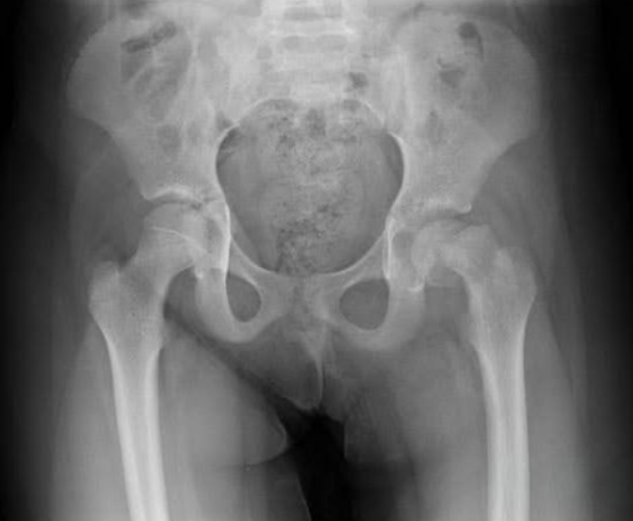

What's the Scoop?

A 13-year-old obese female has had a limp for 3.5 weeks. Her x-ray is shown below.

Not so Hip

An 18-year-old male presented to the Emergency Department after a motor vehicle collision at unknown speeds. Patient was the restrained driver, airbags did deploy, and he’s unsure if he lost consciousness. He is primarily complaining of bilateral hip and right hand pain with notable obligate abduction and external rotation of the right lower extremity on initial inspection.